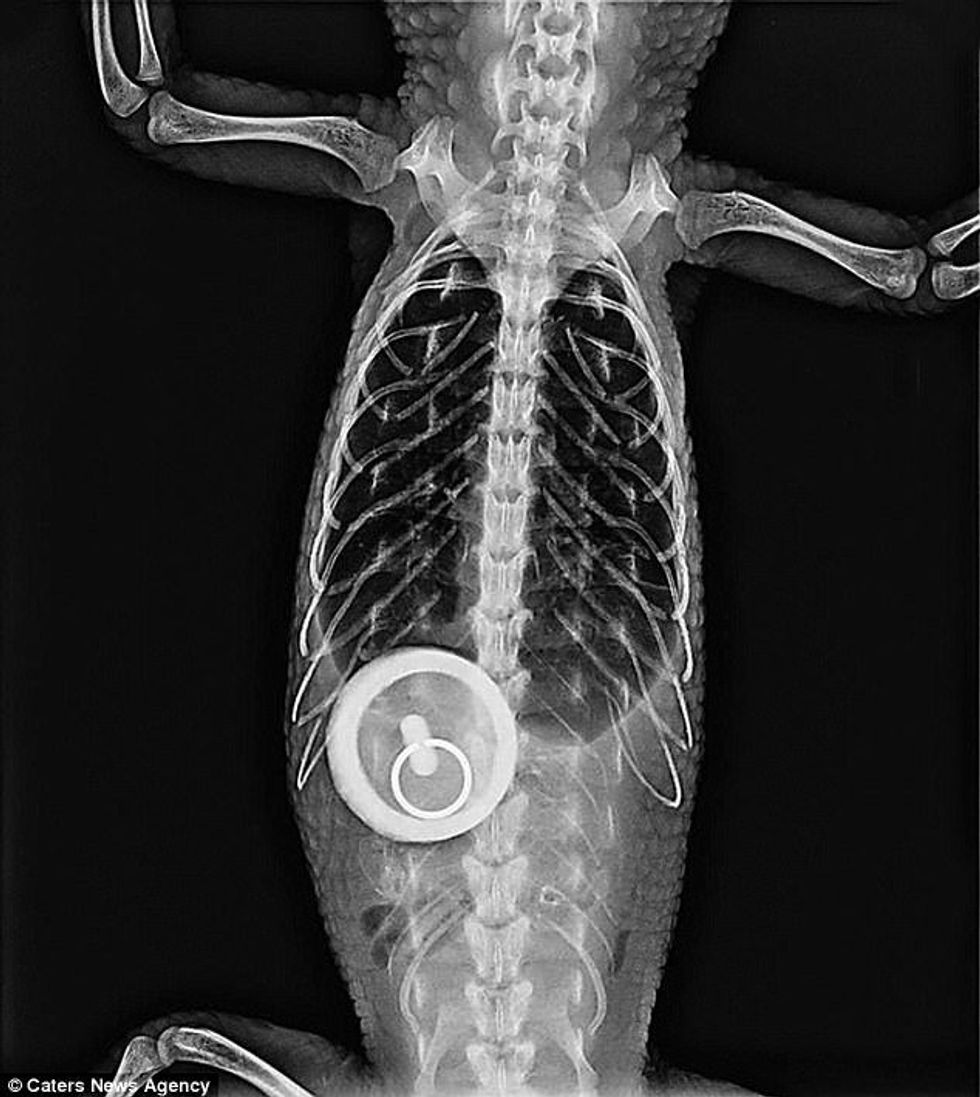

Menjëherë pas tij, ishte një këlysh i vogël, që në bark iu gjet qaforja me një varëse që ngjanë me breshkën.